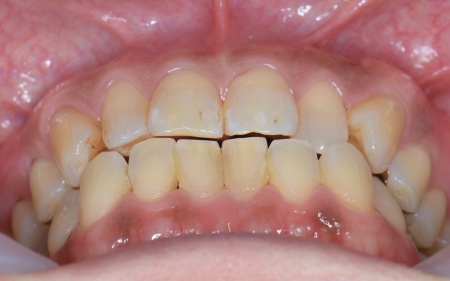

続いて噛み合わせを拝見したところ、前歯がしっかりと噛み合わない開咬(かいこう)という状態です。

この開咬により、本来前歯で分散して受け止めるべき噛む力が、すべて奥歯に集中していることがわかりました。そのため下顎隆起が発生し、また重度歯周病の大きな原因になっていると考えられます。

以上のことから、噛み合わせの問題を根本的に解決しない限り歯周病の治療を行っても再発のリスクが高く、長期的な口腔内の健康維持は困難です。

そのため、歯周病の治療と併せて噛み合わせを改善する必要があると診断しました。

とくに上の左右奥歯には、矯正用ミニインプラント(矯正治療専用の小さなネジ)を埋入し、奥歯を歯茎の方向に押し下げる「圧下」という治療を行っています。これにより開咬が解消され、前歯でしっかり噛めるようになりました。